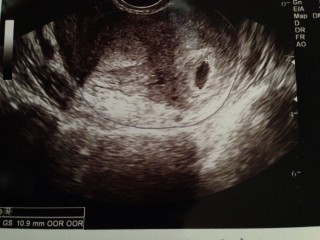

この写真をいただく診察の前日、思いっきり腰から転んでしまい 不安で不安で半泣きで病院に駆け込みました。 赤ちゃんは無事とのことで、10.9mmの胎嚢が確認できました。 私は中隔子宮という子宮奇形なのですが(胎嚢すぐ左の黒い部分が子宮の真ん中にある壁) 1人目は右の部屋でしたが、今回の赤ちゃんは左の部屋にいるそうです。

念のため、安静にという指示が出ました。 1人目の妊娠まで8年かかり、2人目は諦めかけていたのですが 来てくれました。 お姉ちゃんのお世話で、なかなか安静にするのが難しいですが、 できるだけ言い聞かせて2週間後の検診まで過ごしたいと思います。